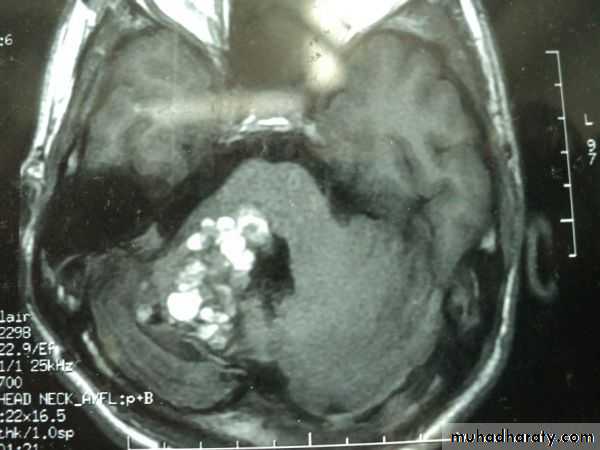

CEREBELLAR CAVERNOUS ANGIOMA AXIAL MRI